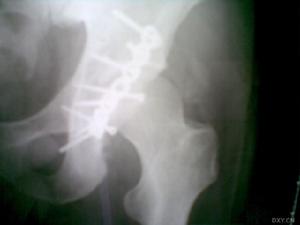

手術治療(2)保守治療後不能緩解症狀可嘗試手術治療。目前治療椎管狹窄症的手術大概分為三類:即單純減壓術、減壓+融合術、微創手術。鑒於許多老年患者的身體不能耐受手術創傷,通過保守治療又不能緩解劇烈腰腿痛症狀,可以選擇微創介入治療技術,該技術在局麻下利用影像學定位技術,將治療精確到病變部位可以迅速解除神經根受壓引起的劇烈根性神經痛。近年來微創手術方法進入脊柱外科領域,如椎間盤髓核溶解術、射頻椎間盤消融、雷射椎間盤消融、臭氧椎間盤消融等,在臨床治療中發揮了重要作用。微創介入技術不需要開刀、不輸血、手術時間短、副作用小、療效可靠、較開刀手術安全和易於被患者接受,因此是治療老年性椎管狹窄疼痛的理想方法。

標準的廣泛椎板切除減壓方法在所有受累的脊柱橫向平面,由側隱窩的外界去除椎板和黃韌帶,受累神經根在直視下從硬膜起始部至神經孔出口的整個行程行徹底減壓,所有嵌壓神經根的側隱窩行減壓,儘管臨床症狀提示僅為單平面狹窄,單側神經根受壓。理由是椎管狹窄是一種多平面疾病,單平面減壓遠期效果不理想有限減壓方法理由是退變性椎管狹窄多為階段性,主要為黃韌帶打折、增生性肥厚、小關節和關節囊的增生以及纖維環膨出所致。在矢狀面骨性椎管常常不狹窄。因而應行選擇性的有限減壓,以保留較多的後部骨和韌帶結構,從理論上講,可減少術後發生脊椎不穩定。

腰椎椎管狹窄症光片植骨融合問題近年來,對腰椎管狹窄減壓術後行融合的作用討論較多。減壓後沒有同時行植骨融合術,已有並發腰椎滑脫的報告,減壓同時行小關節全切,術後腰椎滑脫多達2倍,是術後效果不好的原因之一。但同時行植骨融合術,使手術複雜化,延長了手術時間,增加了失血量,術後併發症增多,康復時間延長,一般認為同時行脊椎融合術對患者康復無益。下列因素應考慮需同時行植骨融合術,伴有退行性椎體滑脫Laus等人報告單純減壓取得成功。這表明由於椎間隙變窄和增生性骨刺的作用,該階段可獲得自然穩定。然而,另有資料表明,同時行滑脫階段融合,有利於改善臨床症狀。Postachini等人報告16例術前有滑脫,術後隨訪8.6年的結果,其中6例單純減壓,另10例同時行融合術,發現未行融合者骨質長入椎管較多,臨床效果不及同時行融合者。近年來的文獻分析資料表明,若同時行滑脫階段融合,可獲得更滿意的手術效果。

復發性椎管狹窄伴有醫源性滑脫時,再次手術必然要考慮植骨融合,以增加脊柱的穩定性。小關節去除過多由於手術時小關節切除或切除>50%會引起不穩定,應同時行脊椎融合術,以防術後脊椎不穩或疼痛。如果至少有一側小關節的完整性保留,脊椎的穩定性就能維持。但是,生物力學研究表明,單側小關節切除後(表明節階活動性明顯增加),即使另一側完整性良好,也將會發生不穩定,單側或雙側小關節內側部分切除(<50%),對脊椎的穩定性影響甚微。脊柱內固定植骨融合是否同時套用內固定器械爭議較多。

④、屈伸位X線片顯示,椎體平移超過4mm,成角大於10°時。內固定方法的選擇應以短階段固定為主,根據術者掌握的熟練程度和病人的實際情況靈活套用。越來越多的資料表明,滑脫行融合術時,同時行內固定是有益的。